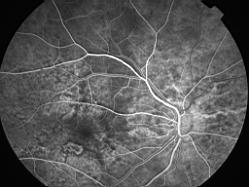

ASSOCIATION STRIES ANGIOIDES ET DYSROPHIE MACULAIRE RETICULEE

NEOVASCULARISATION